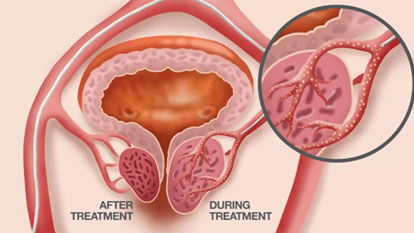

Fallopian Tube Recanalization

Fallopian Tube Recanalization (FTR) is a minimally invasive, image-guided procedure aimed at restoring patency in blocked...